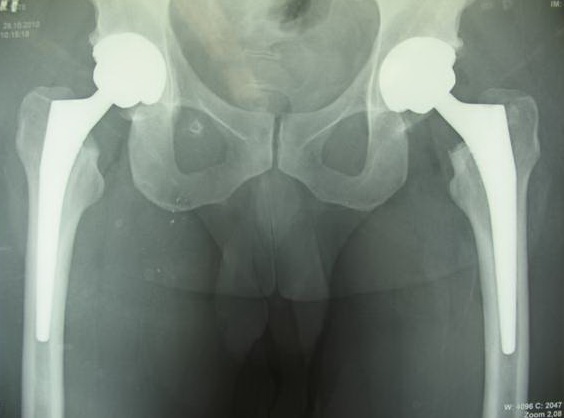

На сегодняшний день общепризнано, что эндопротезирование тазобедренного и коленного суставов является единственным эффективным методом лечения при разрушении суставного хряща и позволяет избавит пациента от боли и вернуть его к активной жизни. В мире ежегодно выполняется более полутора миллионов таких операций. Современные эндопротезы служат десятки лет и позволяют жить полноценной жизнью даже молодым и активным пациентам, а в случае, если эндопротез всё же износился, его можно заменить на более сложный и продолжать пользоваться всеми благами жизни.

Мы имеем опыт более 100 операций одноэтапного двустороннего эндопротезирования тазобедренных суставов.